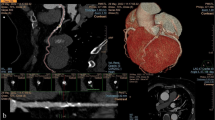

The Bland–Altman analysis of the Agatston CAC score as assessed with both methods is shown in Fig. 4. The non-contrast CT Agatston CAC score was lower compared to the contrast CTA Agatston CAC score as demonstrated by a bias of −176 with 95 %-limits of agreement ranging from −1,248 to 896. The bias on a percentage basis was 3 % with 95 %-limits of agreement ranging from −174 to −168 %. As demonstrated in the Bland–Altman analysis the absolute error increases with increasing CAC-scores (lower panels). However, on a percentage basis this trend is not observed (upper panels).

Bland–Altman of non-contrast CT Agatston CAC score and contrast CTA Agatston CAC score. The left panel shows the Bland–Altman plot. De dotted vertical lines represent the bias with corresponding 95 % limits of agreement. The right panel shows a magnified view of the same Bland–Altman plot with an X axis range of 1,000. In the two upper panels the Y axis represents the percentage difference of the Agatston CAC score between the two methods. In the lower two panels the Y axis represents the absolute difference